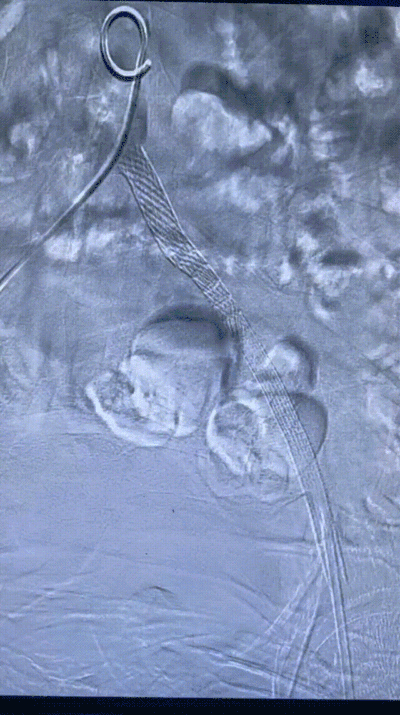

预扩后造影显示管腔打开。导入8F长鞘,通过长鞘输送并植入6X100mm 的VIABAHN 支架。继续通过8F长鞘导入VBX 支架,VBX支架近端定位在髂总动脉开口处,远端重叠在VIABAHN 支架内25mm左右。通过长鞘造影判断VBX支架位置后开始释放支架。根据产品外包装提示,当压力泵压力在6atm时,VBX 支架直径为7.1mm,此时支架会完全展开。故第一次加压6atm,支架顺利展开后排空并回撤球囊。调整球囊位置避开支架重叠区,在髂总动脉开口处再次给球囊加压到11atm,观察到支架直径随球囊的增大发生了扩张。根据产品信息提示此时已到达目标直径8mm。撤出球囊后在腹主动脉做整体造影,髂动脉开通良好。但发现VBX 支架近端与左侧腹主动脉分叉处贴壁不完全,判断是由于球囊后扩张是翻山的形式,使支架跟随了球囊的形态导致,故左侧股动脉入路上8mm直径的球囊在VBX开口处进行贴壁性后扩。支架形态被成功纠正,贴壁良好。

释放6x100mm VIABAHN 支架

导入VBX 支架

6atm压力释放

释放VBX支架,11atm的压力

8mm*6cm P3球囊

术后造影结果

术后造影显示,支架呈现8mm-7mm-6mm的梯度锥形,管腔打开完全,定位精准,贴壁良好。

术后造影